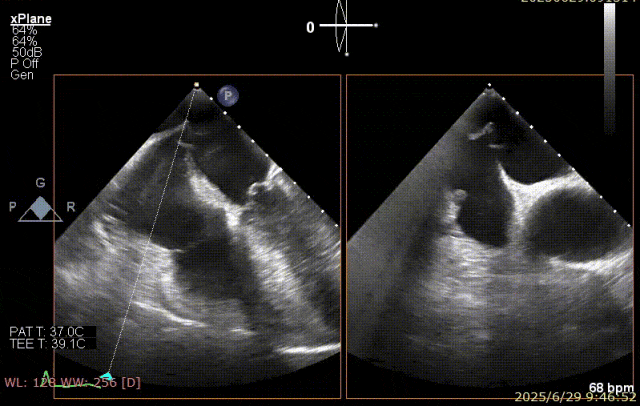

术前超声

患者术前 TEE 可见 P3 区脱垂二尖瓣环前后径(AP)约 37 mm,CC 径约 41 mm,瓣叶无明显钙化及裂隙,后瓣瓣尖探及一长约 9 mm 短带样回声漂附,二尖瓣口面积约 5.3 cm²。

经我院心脏超声检查提示:左房室增大伴二尖瓣后瓣脱垂(P3 区,腱索断裂)并重度关闭不全(Carpentier IIb 型,反流分级 4+);符合高血压性心脏病改变;少至中等量心包积液;左室舒张功能降低,收缩功能测定在正常范围并呈假性高排表现。